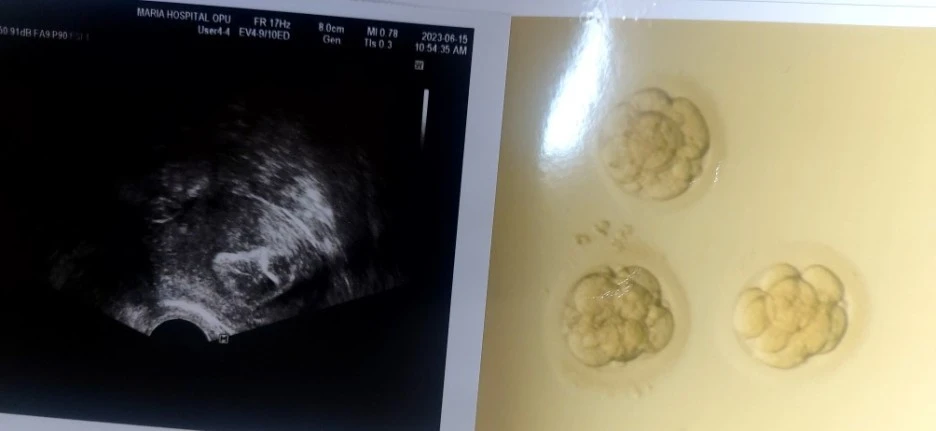

하지만 너무 감사하게도 무려 배아가 4개나 수정되었고 3일 배양 3개를 이식하기로 했다.

선생님이 배아 사진과 이식한 초음파사진을 주시며

이식은 잘 되었다고 하셨는데,,,

왼쪽 위쪽 어디라고 하시는데 아직도 어딘지는 모르겠다.. ㅋ

오른쪽맨위에 모양이 젤 이쁜것부터 시계방향으로 상,중상,하급의 배아인듯?

배아사진을 주는 병원이 있고 안주는 병원도 있는듯,

내가 다니는 마리아 병원은 이런 서비스면에서 환자들의 궁금증은 잘 해결해 주는편인듯 하다.